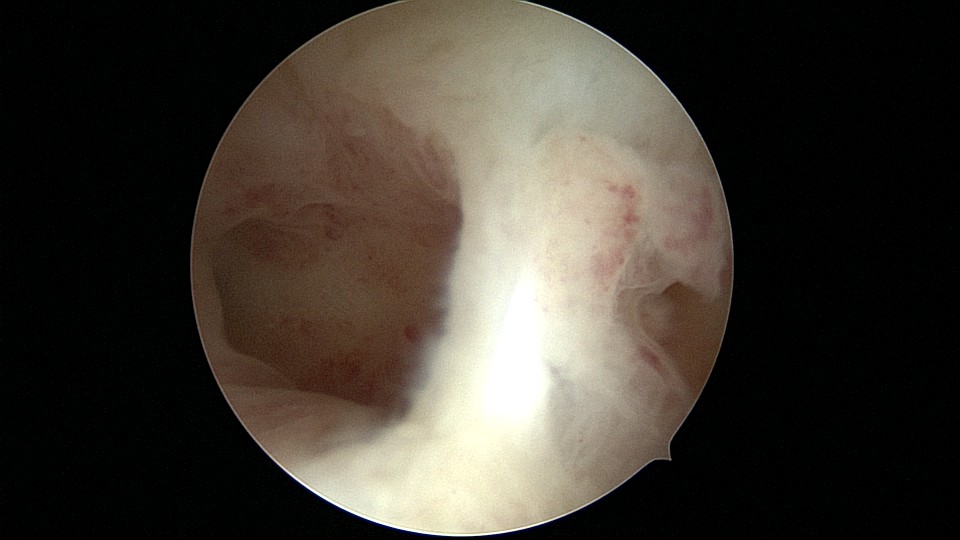

患者28岁,G1P0,2019年11月孕9周胎停1次,药流清宫,术后月经量逐渐减少,淋漓不净。外院B超发现宫腔粘连,2021年6月初宫腔镜探查,宫腔两侧及右侧宫角粘连,单级电针分粘,恢复宫腔形态,显露双侧输卵管开口(术中图像采集系统突发故障,分粘及分粘后图片未采集到)。2021年6月底宫腔镜二探取球囊,宫腔形态正常,双侧输卵管开口可见。2022年12月自然妊娠,足月顺产。现33岁,G2P1。